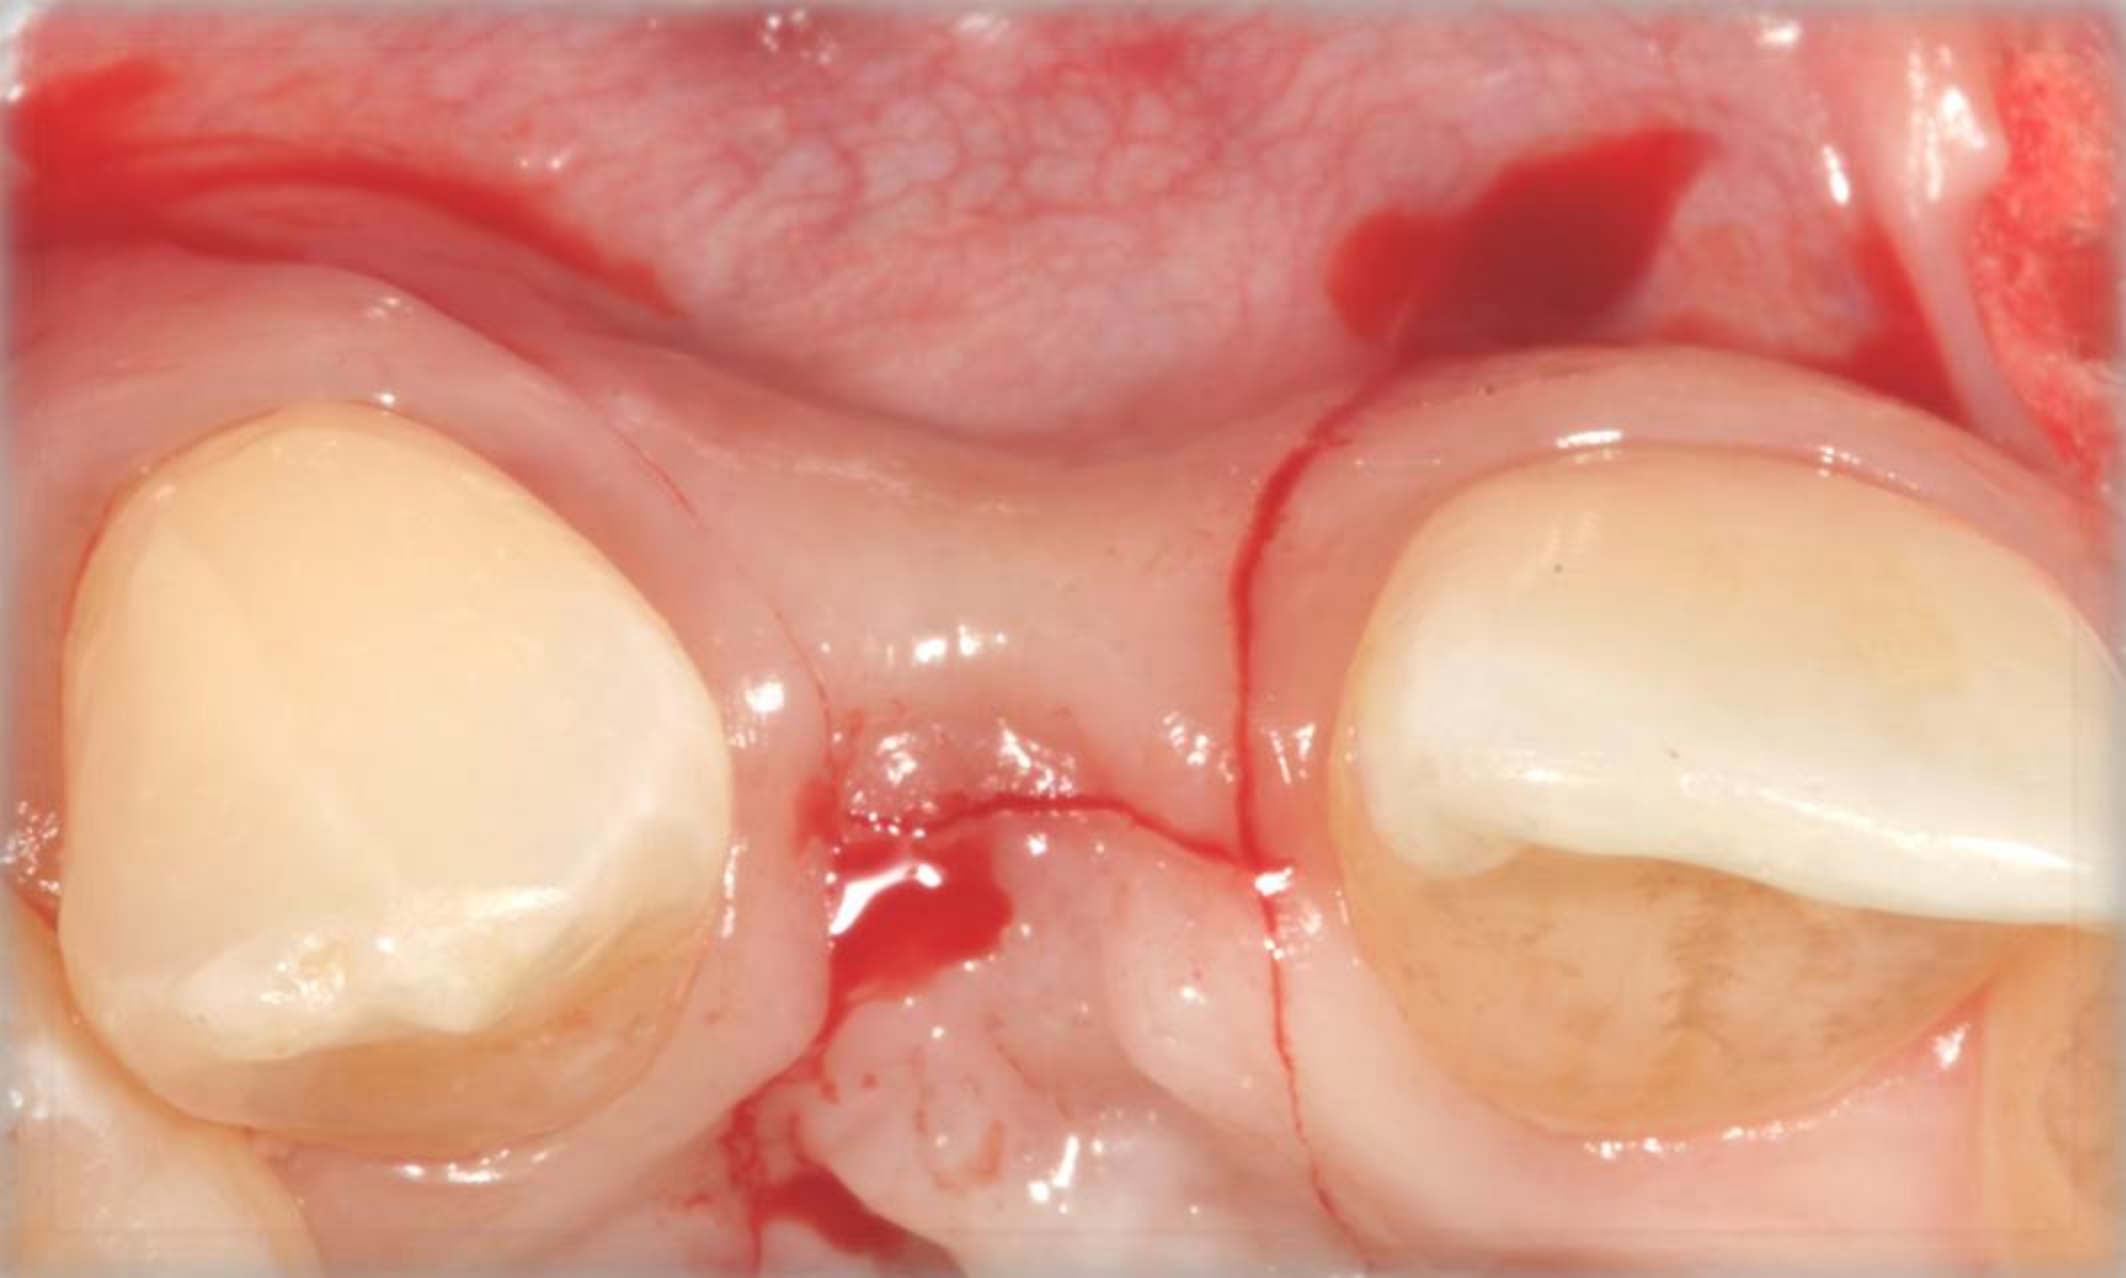

Fig 18. The final restoration after 4 months.

Figure 18